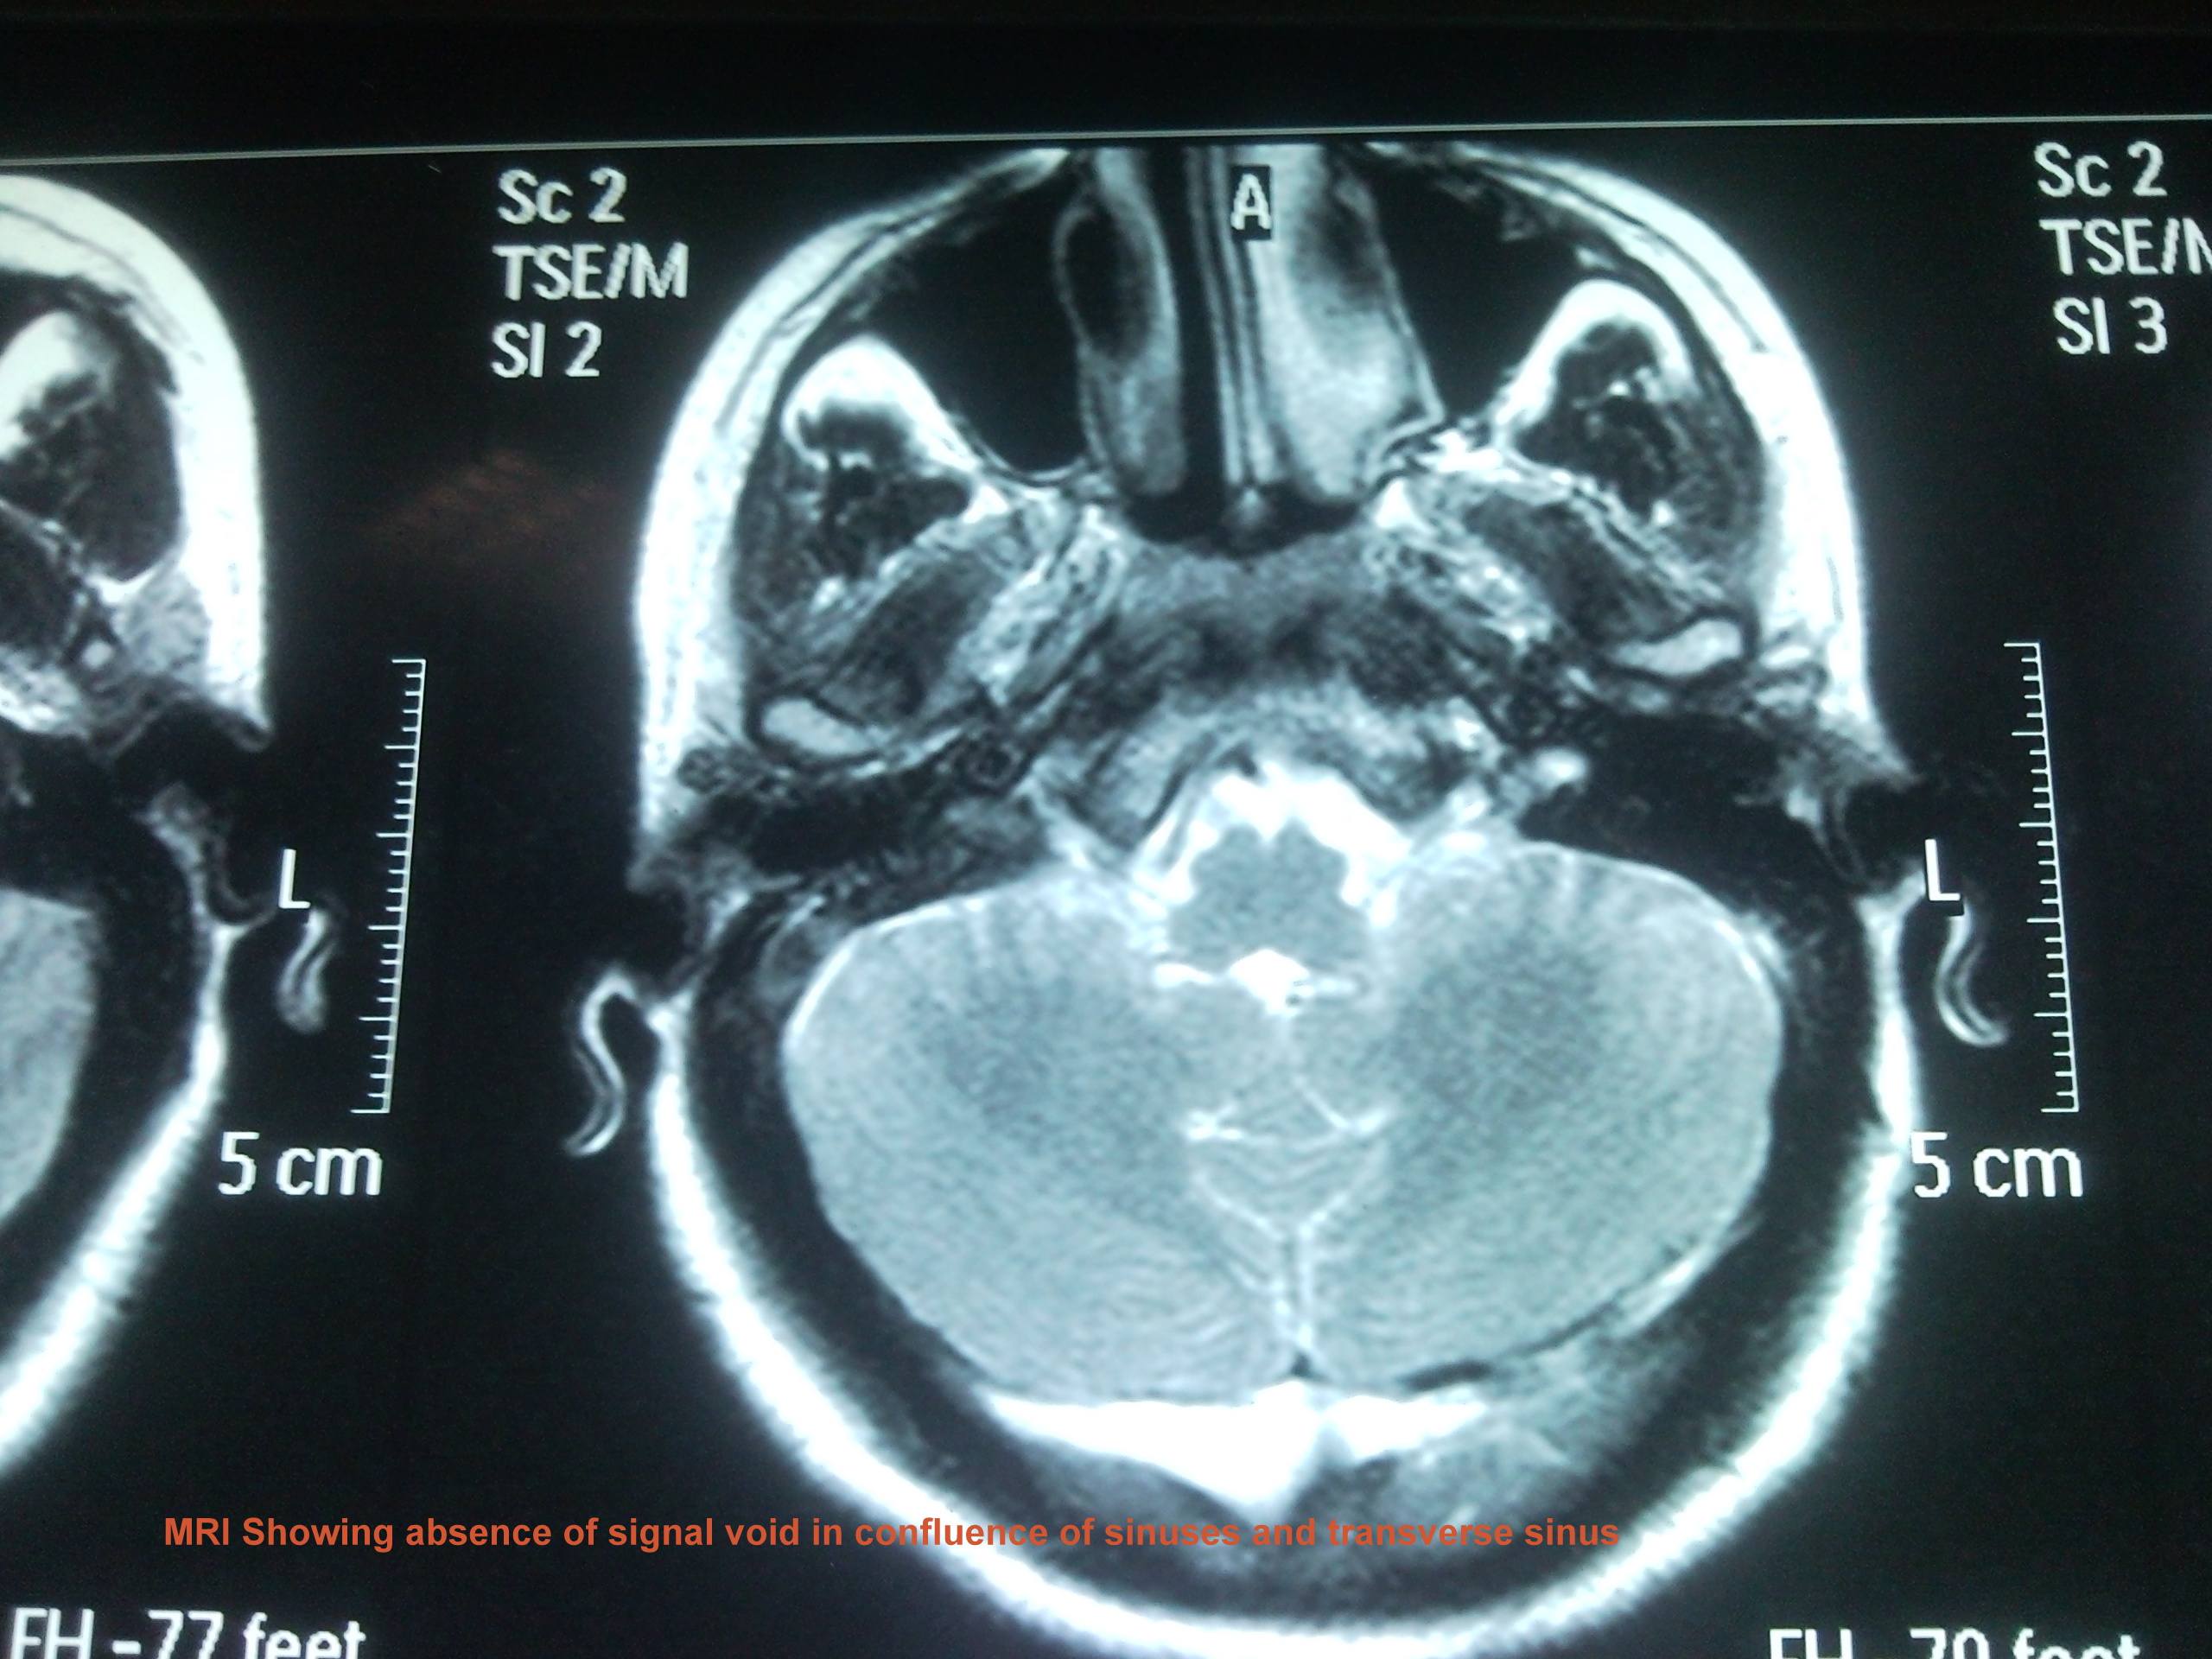

We present a case of 29 years old female patient with 20 days history of headache, projectile vomiting and low grade fever. She was referred from Swat where she was locally treated as acute pyogenic meningitis with no improvement. Patient had right 6th cranial nerve palsy and papilledema. CT brain was unremarkable and MRI brain with MR Venography showed superior sagital, confluence of sinuses and transverse sinus thrombosis.